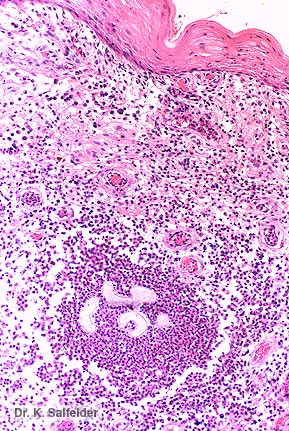

Abb. 16,54: Myzetome

Aktinomyzetom. Druse von Nocardia sp. in einem Abszess.HE-Faerbung